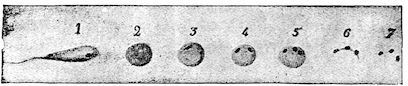

| Intestinal coccidiosis of calves and lambs (Psorospermosis, hæmorrhagic enteritis, bloody flux, dysentery, etc.) | 271 | |||

| Bovine piroplasmosis | 416 | |||

| Bovine piroplasmosis in France | 424 | |||

| Ovine piroplasmosis | 425 | |||